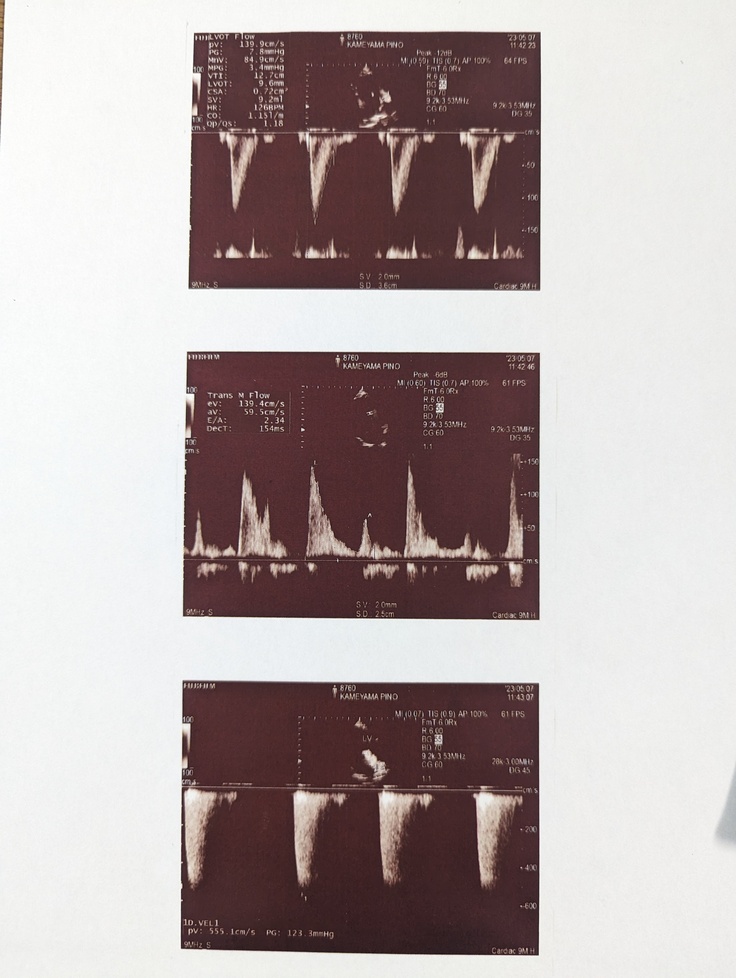

エコーを撮ってもらうと

心臓の僧帽弁閉鎖不全により血液の逆流が起こっていて

心臓に負担がかかっている事が分かりました。

その結果ぴのは先天的に心臓の僧帽弁の腱索が短く

そのせいで僧帽弁の閉鎖不全が起こっている事が分かりました。

僧帽弁がしっかり閉じないことで血液の逆流が起こり

逆流した血液が心臓内に溜まり心臓を押し広げ心拡大が進行します。

調べた時点でぴのの心臓の拡大は進行してしまっていて

いつ心不全や肺水腫を起こすか分からないと言われました。

(拡大が進行しているぴのの心臓)